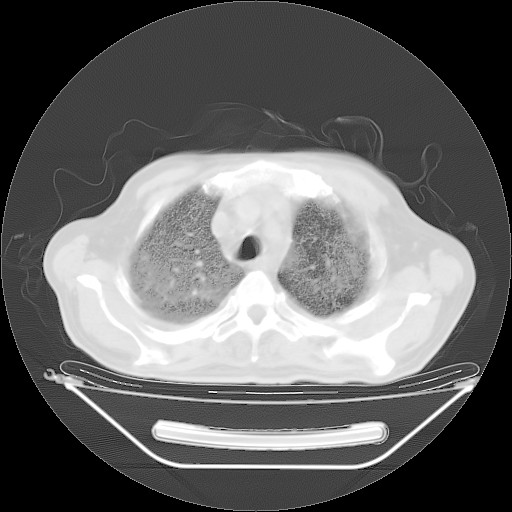

今天复查肺部CT,发现双肺广泛磨玻璃样改变。所以我把3月19日和5月9日相隔50天的肺部CT上传。请大家会诊。

2009年3月19日肺部CT片。

2009年3月19日肺部CT

大致读了系列胸部CT:纵隔窗无明显异常,肺窗:从4、27至今:主要是双肺中下野外带可见毛玻璃样改变,目前处于急性肺泡炎阶段,至于原因考虑1、结替组织或胶原血管性疾病所致?2、恶性疾病如恶组在肺部所致的表现或细支气管肺泡癌?3、药物或其它原因如肺蛋白沉着症所致肺泡炎目前不太可能?总之,明天就去请我院的呼吸科、感染科、血液科和临免专家会诊哈。